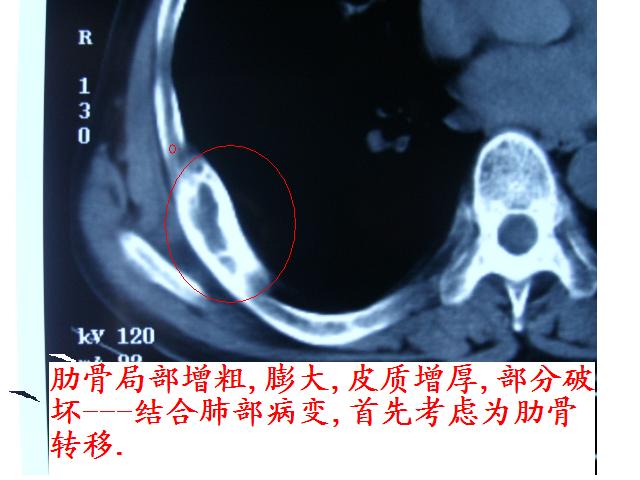

肋骨应该不是转移,其为膨胀性改变,边缘增厚硬化,临近软组织未见明显异常改变,考虑骨纤等病变。

单纯肋骨局限性膨胀,边界清楚,皮质增生硬化,考虑:1  请详细了解病史,除外陈旧骨折.2 骨纤维异常增埴症

右肺内病变考虑肺癌,右侧肋骨局部增粗,皮质增厚,髓腔增宽,有否陈旧骨折?先考虑骨纤维异常增殖症。

1.右下肺病灶周围型肺癌的可能性非常大。

2.右侧肋骨病变转移的可能性非常小,首先考虑骨母细瘤。次则考虑骨纤维异常增殖症。

建议详细询问病史,排除陈旧性骨折所致。